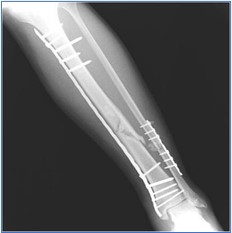

Osteosynthesis

Internal fixation offers an ideal alternative to traditional casts and splints. the American Academy of Orthopaedic Surgeons (AAOS)  ranked “internal fixation” among the top significant treatment advances of the 20th century.Medical bone plates and screws are used  for a variety of trauma conditions and disorders. Orthotek provides testing services up to ASTM and ISO standards as well as client demands.

Screws & Plates